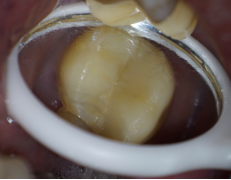

患者牙齿中间可以看到清晰的裂纹。

患者牙齿顺着裂纹用探针勾开的样子。